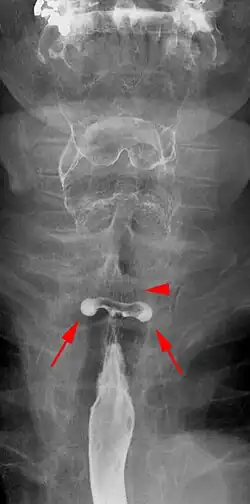

Das Killian-Jamieson-Divertikel ist wie das viel häufigere Zenker-Divertikel ein Pulsionsdivertikel am oberen Speiseröhren-Sphinkter. Es hat seinen Ursprung jedoch unmittelbar unterhalb des Sphinkters und ist somit im Gegensatz zum Zenker-Divertikel tatsächlich ein Divertikel der Speiseröhre.

Killian-Jamieson-Divertikel können als permanente Form (Divertikel auch in der Ruhephase zwischen zwei Schluckakten erkennbar) mit den transienten Pouches dieser Region (nur während des Schluckens hervortretend) zusammengefasst werden.

Die Lokalisation nach ventrolateral unmittelbar unter dem Musculus cricopharyngeus oder nach dorsal durch das Laimer-Dreieck ergibt sich durch die anatomischen Schwachstellen hier. Mitursächlich sind Druckspitzen zwischen einzelnen Muskelpartien der obersten Anteils der Speiseröhre.

Killian-Jamieson-Divertikel erreichen selten eine Größe von mehr als 1,5 cm. Divertikelträger sind in der Regel symptomlos, was sich dadurch erklärt, dass eventuell retinierte Speisereste nicht wie beim Zenker-Divertikel nach oben in den Pharynx oder in die Luftwege gelangen können.